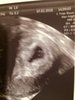

Moje Cudo - 1,1mm i widać już lekko bijące serduszko [emoji2][emoji2][emoji2] Co za radość,poryczalam się na fotelu,mój M tez miał łzy w oczach [emoji4] następna wizyta 25.01 i wtedy ma już walić jak dzwon [emoji4] A Bąbelek wybrał sobie w macicy miejsce (jak powiedział lekarz) "mistrzostwo świata".

• IMG_3898.jpg

929,9 KB · Wyświetleń: 823